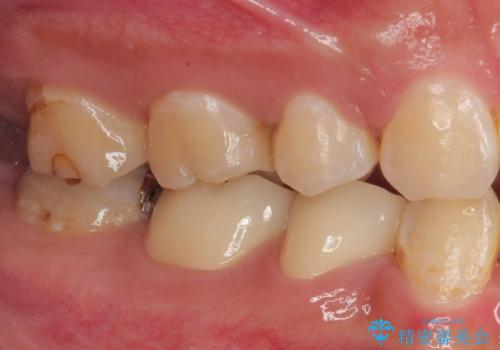

- 当院にて矯正治療を終えた患者様で銀歯を白くしたいとのことで来院された患者様です。神経の反応を確認し詰め物の範囲も大きいためフルジルコニアクラウンにて治療を行うことにしました。

拡大鏡視野下でメタルインレー、虫歯を除去しフルジルコニアクラウンに適した形に整えました。